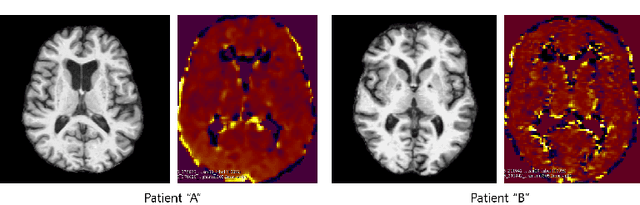

Abstract:Positron Emission Tomography (PET) is now regarded as the gold standard for the diagnosis of Alzheimer's Disease (AD). However, PET imaging can be prohibitive in terms of cost and planning, and is also among the imaging techniques with the highest dosage of radiation. Magnetic Resonance Imaging (MRI), in contrast, is more widely available and provides more flexibility when setting the desired image resolution. Unfortunately, the diagnosis of AD using MRI is difficult due to the very subtle physiological differences between healthy and AD subjects visible on MRI. As a result, many attempts have been made to synthesize PET images from MR images using generative adversarial networks (GANs) in the interest of enabling the diagnosis of AD from MR. Existing work on PET synthesis from MRI has largely focused on Conditional GANs, where MR images are used to generate PET images and subsequently used for AD diagnosis. There is no end-to-end training goal. This paper proposes an alternative approach to the aforementioned, where AD diagnosis is incorporated in the GAN training objective to achieve the best AD classification performance. Different GAN lossesare fine-tuned based on the discriminator performance, and the overall training is stabilized. The proposed network architecture and training regime show state-of-the-art performance for three- and four- class AD classification tasks.

Abstract:Synthesizing medical images, such as PET, is a challenging task due to the fact that the intensity range is much wider and denser than those in photographs and digital renderings and are often heavily biased toward zero. Above all, intensity values in PET have absolute significance, and are used to compute parameters that are reproducible across the population. Yet, usually much manual adjustment has to be made in pre-/post- processing when synthesizing PET images, because its intensity ranges can vary a lot, e.g., between -100 to 1000 in floating point values. To overcome these challenges, we adopt the Bidirectional Encoder Representations from Transformers (BERT) algorithm that has had great success in natural language processing (NLP), where wide-range floating point intensity values are represented as integers ranging between 0 to 10000 that resemble a dictionary of natural language vocabularies. BERT is then trained to predict a proportion of masked values images, where its "next sentence prediction (NSP)" acts as GAN discriminator. Our proposed approach, is able to generate PET images from MRI images in wide intensity range, with no manual adjustments in pre-/post- processing. It is a method that can scale and ready to deploy.